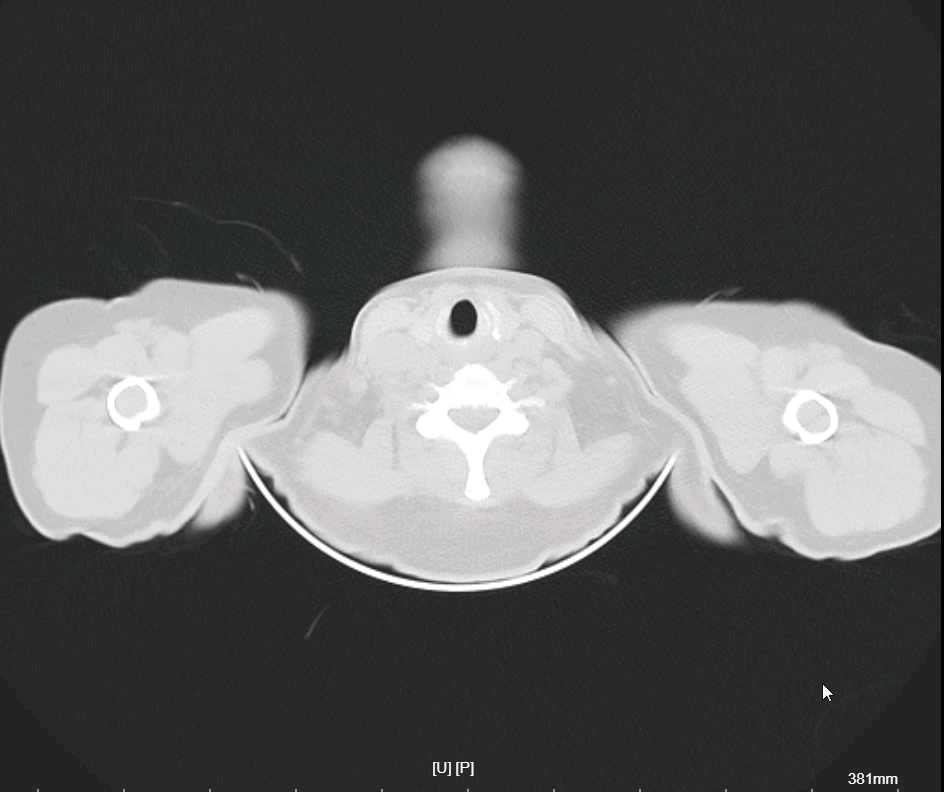

2、既往史:患者既往有“糖尿病”病史数年余,峰值不详,间断服用降糖药(具体用药及剂量愂不详,血糖控制不佳;有“心脏病”病史,否认有“高血压”病史,有药物过敏史(具体诉说不清),无“结核、肝炎、疟疾”等传染病史,曾因外伤导致右下肢骨折,在临沧市人民医院行钢板内固定手术(具体诉说不清);无输血史,预防接种史不详。

4、辅助检查:(2024-06-20)入院心电图示:窦性心律,心率79次/分。入院空腹血糖为:15.5mmol/L。(2024-06-20)入院血常规及超敏C反应蛋白示:白细胞计数:46.11x10^9/L↑↑;中性粒细胞绝对值:33.47x10^9/L↑;淋巴细胞绝对值:4.01x10^9/L↑;单核细胞绝对值:7.10x10^9/L↑;嗜酸性粒细胞绝对值:1.48x10^9/L↑;淋巴细胞百分比:8.70%↓;单核细胞百分比:15.40%↑;红细胞计数:3.19x10^12/L↓;血红蛋白浓度:91g/L↓;红细胞压积:27.5%↓;血小板:87x10^9/L↓;血小板压积:0.09%↓;大型血小板细胞数:22x10^9/L↓;C反应蛋白:6.66mg/L;糖化血红蛋白:10.3%↑;入院尿液分析示:尿胆原:+1;蛋白质:+2;尿白细胞:+3;葡萄糖:+-;比重:1.030↑;维生素C:+2;

1、头痛、头昏查因—1)脓毒症?2)血液系统疾病待排;3)急性脑梗死(脑干?小脑?)4)其它待排;2、2型糖尿病伴血糖控制不佳;3、2型糖尿病性肾病?4、社区获得性肺炎;5、泌尿道感染;6、冠心病待排;7、轻度贫血原因待查;8、血小板减少;9、电解质代谢紊乱?